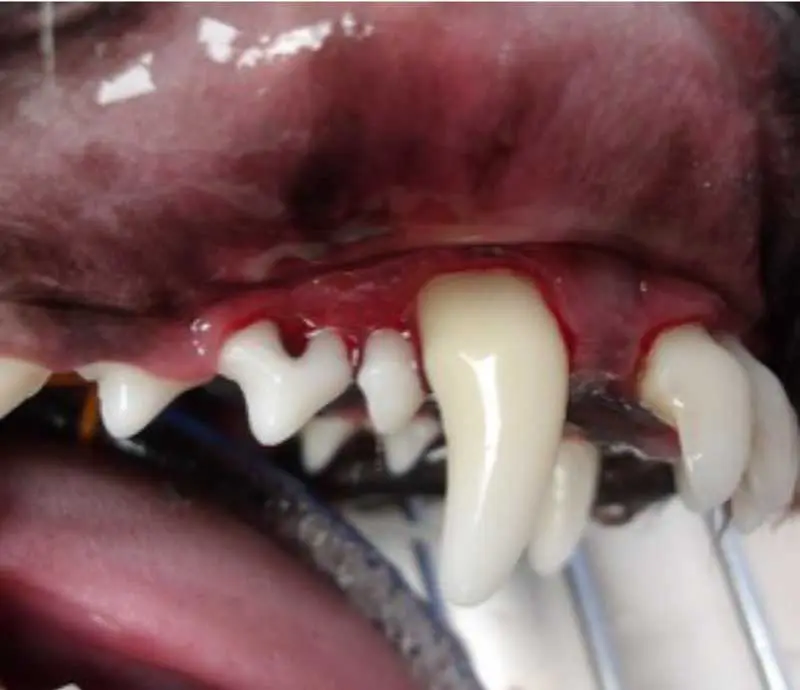

Gingivitis is the mildest form of periodontal disease (Figure 2). At this stage, the gingiva becomes inflamed. Plaque forms at the gingival margin, but the attachments and surrounding bone are unaffected.

Remember that plaque is not always visible to the naked eye, so applying a plaque-disclosing solution can help highlight any areas which may be of concern (Figure 3). Gingivitis is usually reversible with appropriate home care, and symptoms may include:

- Redness of the gingiva.

- Bleeding from the gingiva (severe gingivitis).

- Oedema of the gingival margin.

- Mild halitosis.

- Mild discomfort when the pet eats or chews.

- Gingivitis may also be associated with tooth resorption, oral mass, autoimmune disease, or trauma.